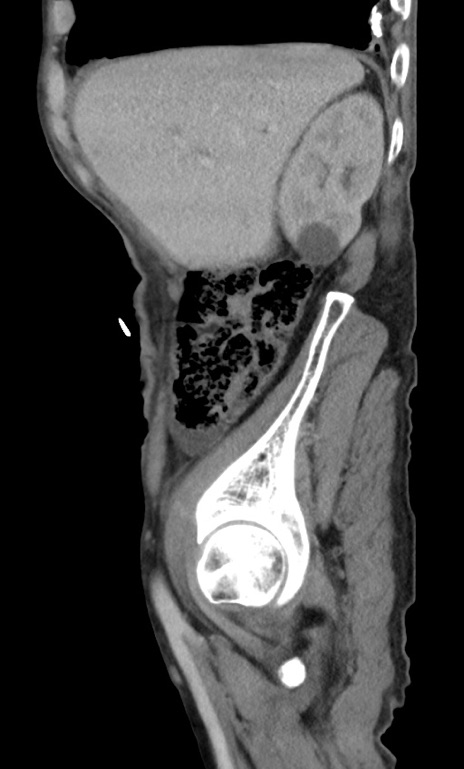

症例3(矢状断像)

【症例】 70歳代男性

【主訴】右鼠径部腫瘤、疼痛

【現病歴】本日朝より上記主訴あり、受診。

【既往歴】膀胱癌にて膀胱全摘、両側尿管皮膚瘻

【データ】WBC 5600、CRP 0.56